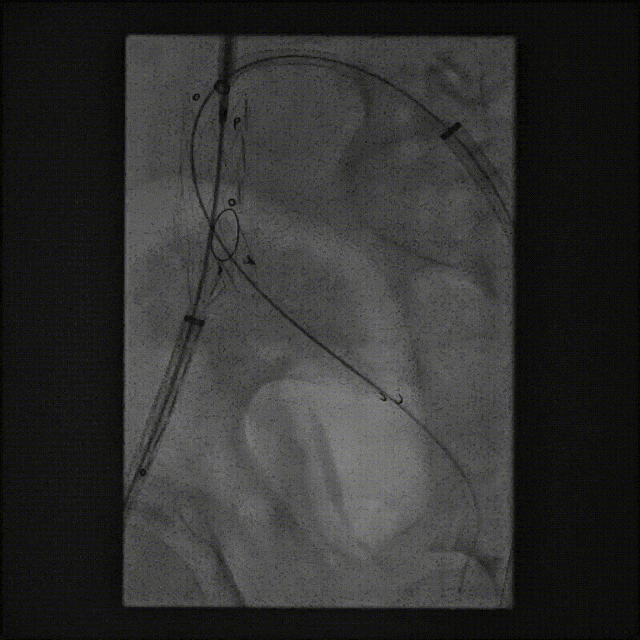

案例一(巨大成角瘤颈):患者瘤颈虽长但呈90度成角。在完成髂动脉重建后,采用Reverse技术释放主体支架。术中造影显示,支架完美贴合扭曲的血管大弯侧,术后一月复查CTA,原有的少量内漏已完全消失。

案例二(短瘤颈+梯形瘤颈):患者近端瘤颈长度不足1cm,且伴有大量附壁血栓。选用适当oversize的支架,结合Reverse技术释放,支架主体自动“寻找”并适应最佳的贴附区域,最终造影显示无明确内漏。